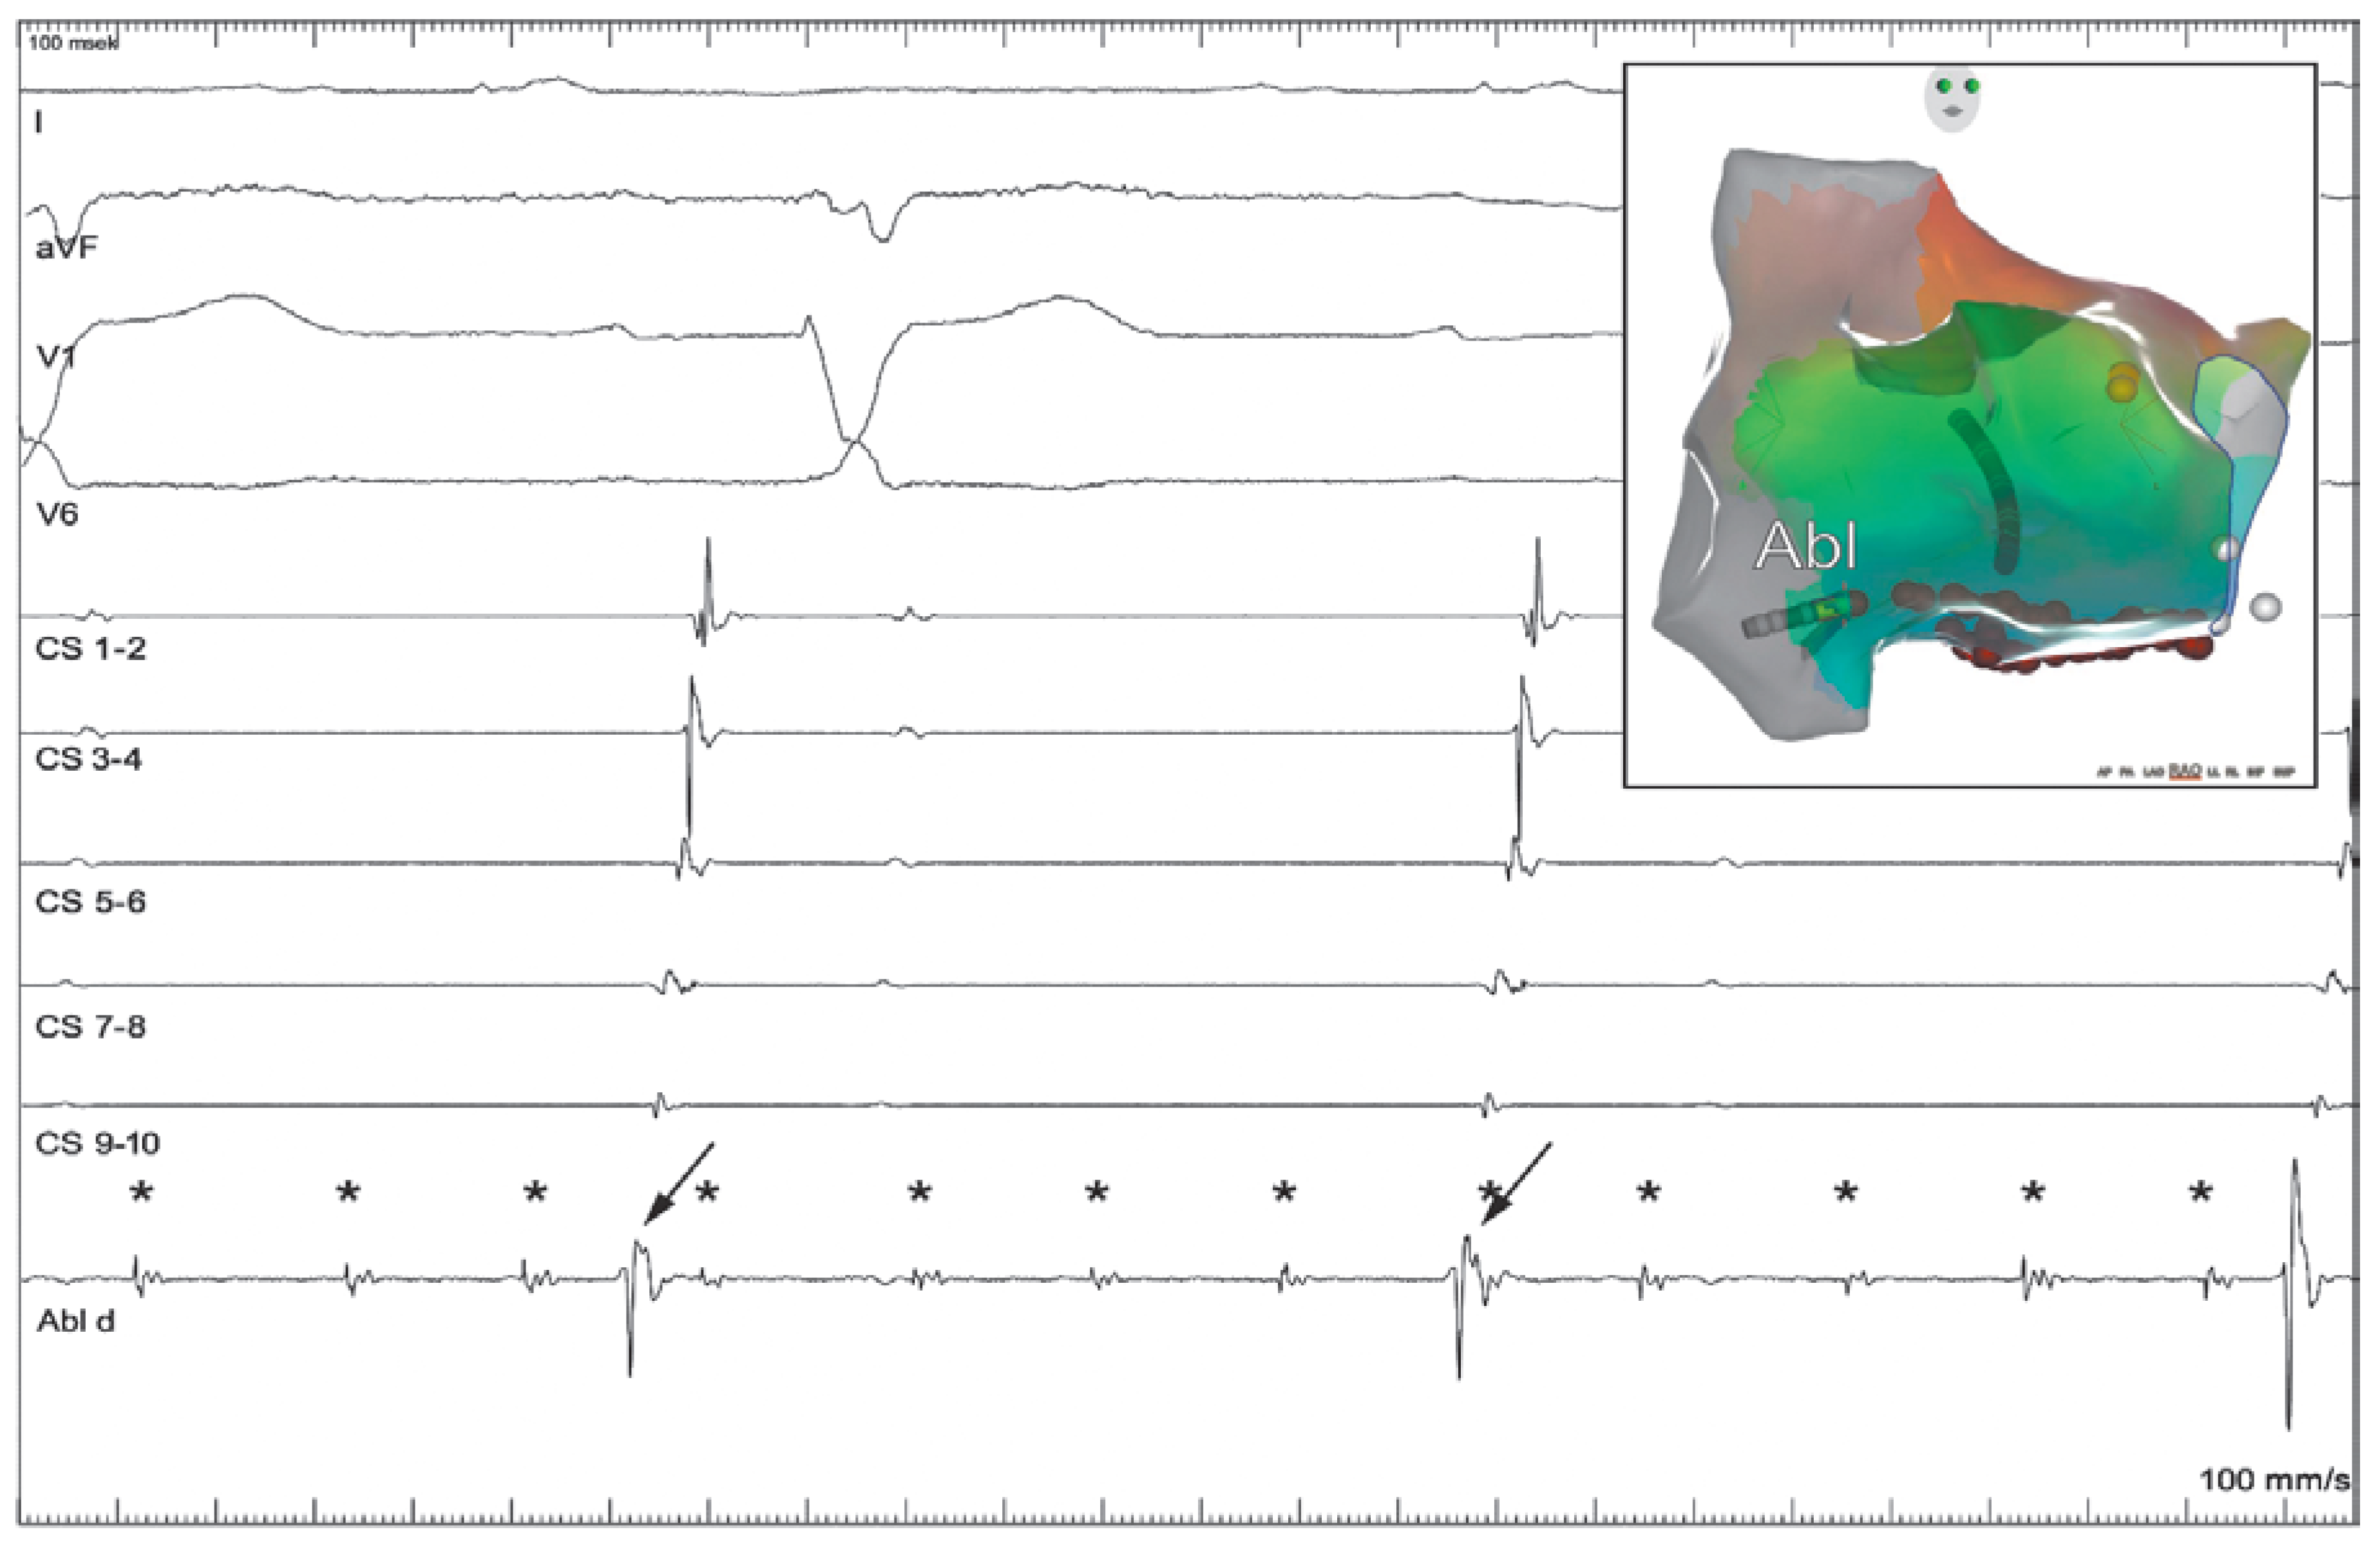

Dual Tachycardia Involving the Cavotricuspid Isthmus and Eustachian Ridge

Case report